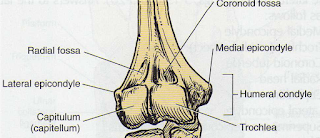

a. Humerus

Humerus merupakan tulang panjang pada lengan atas, yang berhubungan dengan skapula melalui fossa glenoid. Di bagian proksimal,

humerus memiliki beberapa bagian

antara lain leher anatomis, leher surgica,

tuberkulum mayor, tuberkulum minor dan sulkus intertuberkular. (Syaifuddin, 2006) dan bagian

distal, humerus memiliki beberapa bagian antara lain condyles, epicondyle lateral,

capitulum, trochlear, epicondyle medial

dan Olecranon (di sisi posterior).

Tulang ulna akan berartikulasi dengan

humerus di Olecranon, membentuk sendi engsel. Pada tulang humerus ini juga terdapat

beberapa tonjolan, antara lain tonjolan untuk otot deltoid. (sectiocadaveris.wordpress.com/artikel../anatomi-sistem-rangka/26-02-2011)

Gambar 2.1 Anatomi distal Humerus sinistra

(Bontrager, L. Kenneth 6 th Edition.)